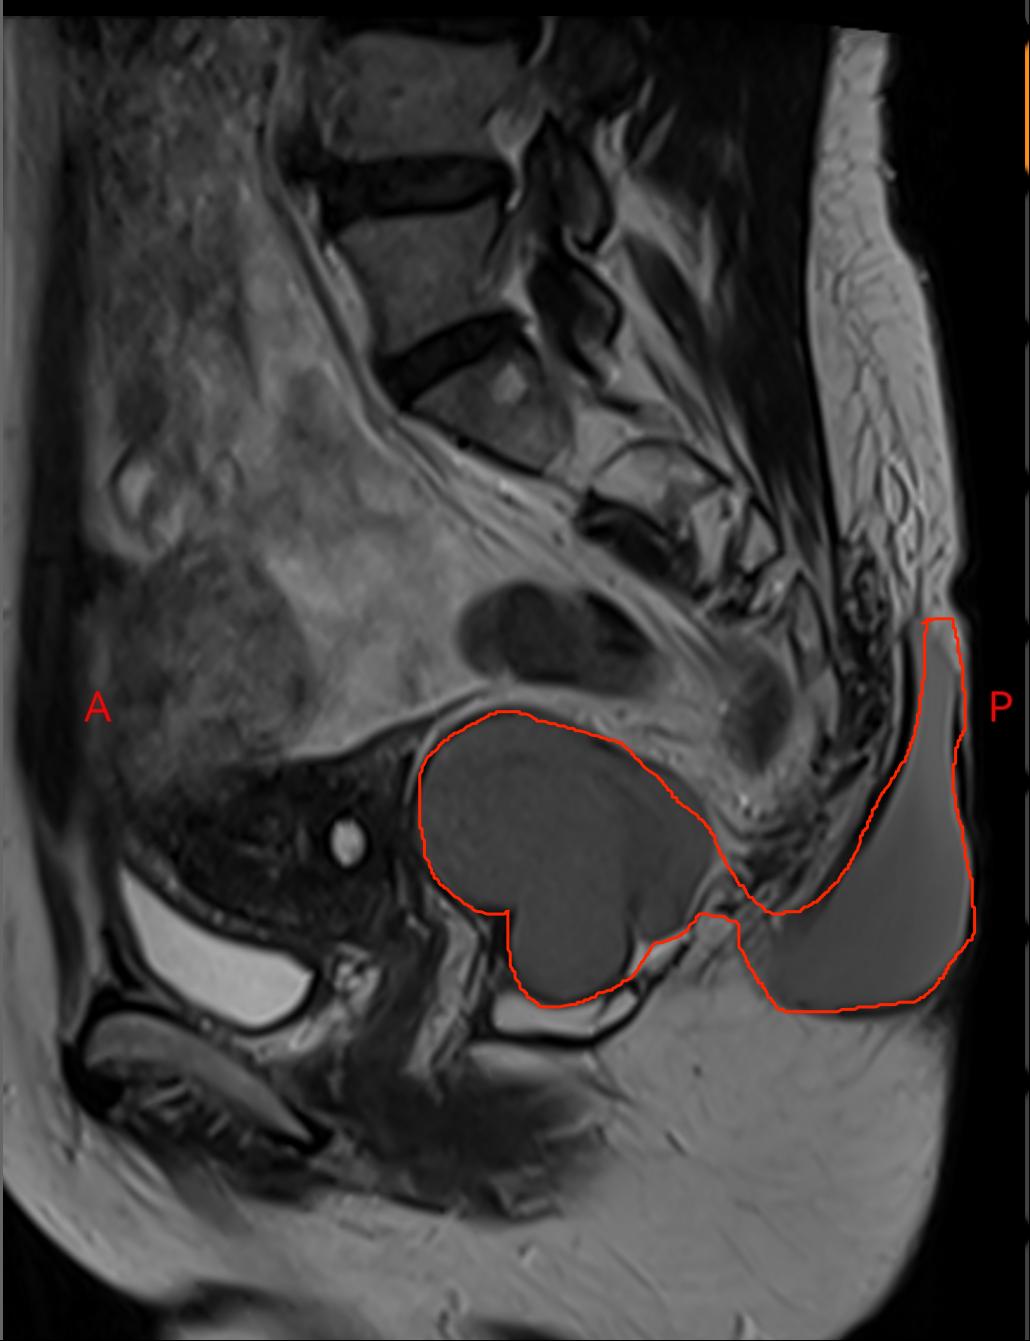

骶尾部皮下囊性占位

从磁共振上看,这个包块有两部分,像个亚油葫芦一样,肚子里面一半,外面一般,外面的那一半像是从尾骨里面挤出来的一样,与肛门周围的肌肉和直肠的关系非常密切,已经不是一个简单的门诊囊肿切除的小手术了,这个一个非常特殊的骶前发育性囊肿。

磁共振显示为葫芦样囊肿